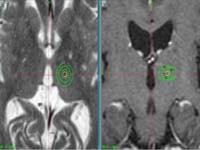

<³úÁ¤µ¿¸Æ±âÇü>

½Ã»óµ¿

ÀÎÁ¢ºÎ ºÎÀ§ÀÇ ³úÁ¤µ¿¸Æ±âÇüÀÇ MRI¿Í Ç÷°üÁ¶¿µ¼ú

¼Ò°ß